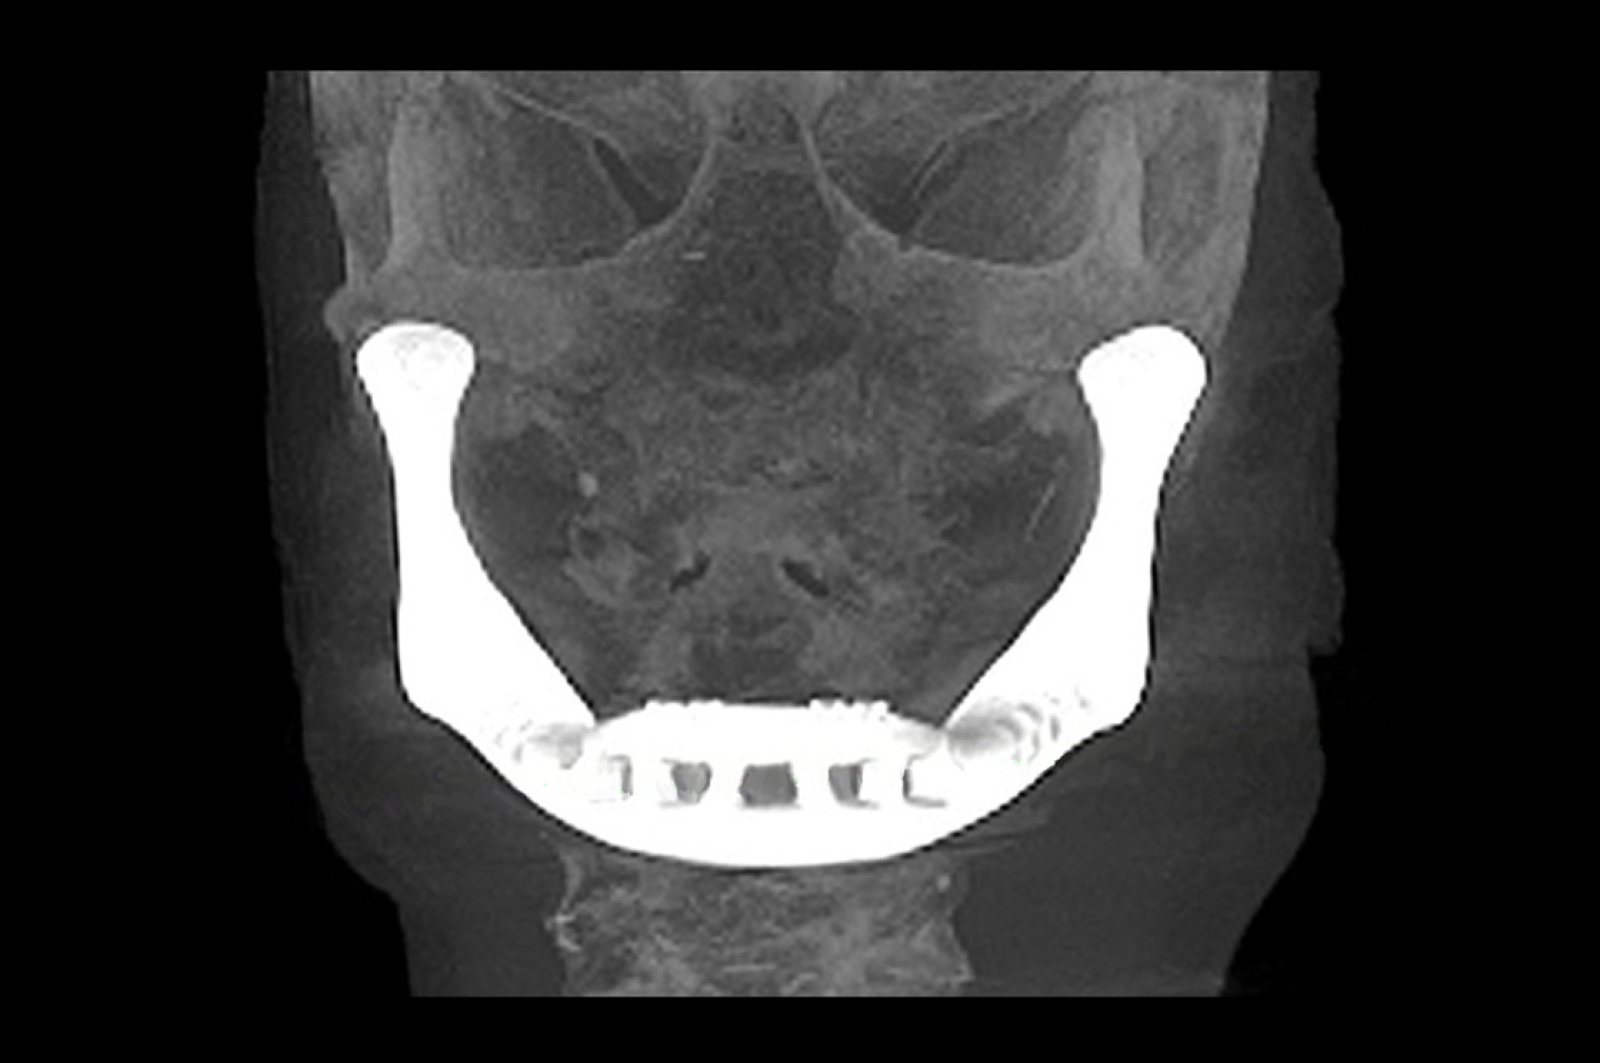

Un equipo de investigadores belgas ha trasplantado, por primera vez, una mandíbula artificial confeccionada a partir de una impresora 3D en el rostro de una mujer de 83 años que padecía una grave infección.

El diseño y la estructura de la mandíbula inferior fueron creados a partir de tecnología 3D. La pieza fue esculpida a partir de polvo de titanio -soldada con láser- que luego se recubrió con plasma y hueso artificial.

Por este motivo, los médicos decidieron realizar el implante de la prótesis artificial fabricada por la compañía holandesa Xilloc Medical BV y solo tardaron cuatro horas, una quinta parte que una operación tradicional.